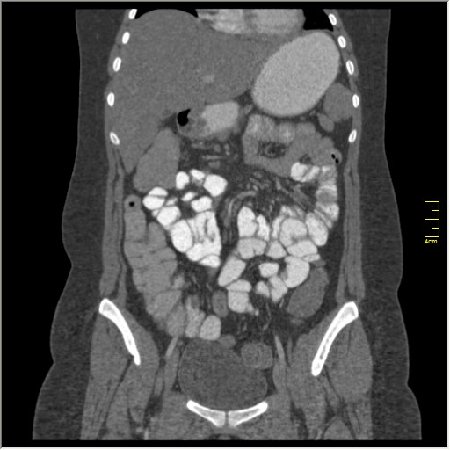

Демонстрационные изображение, оцените возможности метода! Толщина среза реконструкции 0.5-1 мм.